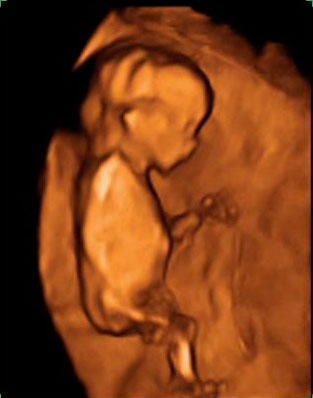

Ecografía 3D de la semana 11: Feto de perfil

En la ecografía en 3D de este feto de 11 semanas de embarazo se pueden distinguir sus extremidades superiores e inferiores ya formadas, así como el esbozo de las orejas y una incipiente nariz.

Ecografía 3D de feto de 11 semanas, de perfil

Este bebé tiene tan sólo 11 semanas de gestación, pero ya podemos identificar muchos de sus órganos y estructuras básicas (huesos del brazo y la pierna, fontanela, ojo, nariz y oreja...). Puede apreciarse el cordón umbilical y la pared uterina sobre la que se apoya.